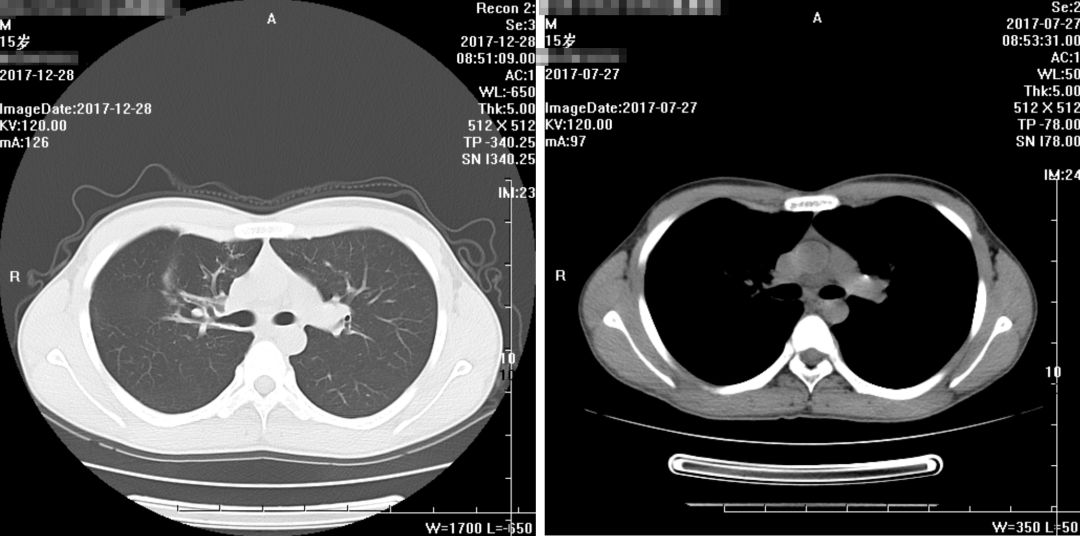

(2017年7月27日)

(2017年12月28日)

复查胸部CT报告:

1、右肺病变较前略有变化,部分减轻,尖段病变增多,请结合病原学检查;

2、右侧少许胸腔积液基本吸收;

3、纵隔及两侧腋窝多发淋巴结部分稍增大,较前未见明显变化。

余大致同前。